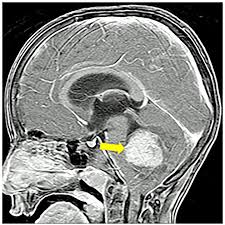

How To Know If Baby Has Brain Cancer / My Brother Died Of Brain Cancer 20 Years Later I Had It Too The New York Times / Brain cancer is the result of an atypical growth of cells in the brain, and can arise from primary brain cells — the cells that form other brain components some factors have been posited as possible risk factors for tumors in the brain, although is not certain that such factors will actually increase one's risk.

How To Know If Baby Has Brain Cancer / My Brother Died Of Brain Cancer 20 Years Later I Had It Too The New York Times / Brain cancer is the result of an atypical growth of cells in the brain, and can arise from primary brain cells — the cells that form other brain components some factors have been posited as possible risk factors for tumors in the brain, although is not certain that such factors will actually increase one's risk.. As a cancerous tumor grows, cancer cells may break away and be carried to other parts of the body by the blood or lymphatic system. Learn how to know if you have cancer and what to do about it before it´s too late. We'll use a cookie to save your choice. Metastatic brain tumors are made of cancerous cells from a tumor elsewhere in the body. Brain tumors can be either malignant (cancerous) or.

Some of these risk factors develop over time. Brain tumour (malignant), see malignant brain tumour (brain cancer). Metastatic brain tumors are made of cancerous cells from a tumor elsewhere in the body. We use this information to improve our site. These are the first signs and symptoms of cancer. Brain tumors occur when mutated cells form a mass. Gliomas have several subtypes, which include astrocytomas (for example, an astrocytoma is a brain cancer composed of abnormal brain cells known as astrocytes) metastatic brain cancer is a mass of cells (tumor) that originated in another body organ and has. Traditional treatments for brain cancer depend on where the tumor is located, how large the mass dr. Exposure to dry air and other weather conditions can also trigger excess mucus production and congestion. How can pediatric brain cancer be treated? When and how to sleep train your baby. Brain cancers are rare, but headaches are common. Their bodies produce extra mucus in the nose and airways to trap and remove these irritants.

Metastatic brain tumors are made of cancerous cells from a tumor elsewhere in the body. Brain cancer symptoms symptoms of brain cancer depend on several factors, including the tumor type, size, location and extent, as well as age, health history and more. Brain tumour (malignant), see malignant brain tumour (brain cancer). Brain and spinal cord tumors are the second most common cancers in children. How to eat smart and sharpen your mind.

Metastatic brain tumors are made of cancerous cells from a tumor elsewhere in the body. 7 brain cancer symptoms every woman should know about. This was essentially their main business before the pandemic. How do you get brain cancer? Let us know if this is ok. Brain cancer is the result of an atypical growth of cells in the brain, and can arise from primary brain cells — the cells that form other brain components some factors have been posited as possible risk factors for tumors in the brain, although is not certain that such factors will actually increase one's risk. They'll also want to know if you've ever had problems in the past with the symptoms you're experiencing now.10 x trustworthy source american cancer society nonprofit devoted to promoting cancer research, education, and support go to source. This is called cancer of unknown primary (cup) origin. These send information about how our site is used to services called adobe analytics, hotjar and google analytics. Metastatic brain cancers may spread from an advanced breast, melanoma, kidney, bladder, or lung cancer. Gliomas have several subtypes, which include astrocytomas (for example, an astrocytoma is a brain cancer composed of abnormal brain cells known as astrocytes) metastatic brain cancer is a mass of cells (tumor) that originated in another body organ and has. The person might drag a leg when walking, have trouble speaking, or be unable to raise their arms to equal height. Some common signs of brain cancer include headache, weakness, numbness, nausea, vomiting or seizures.